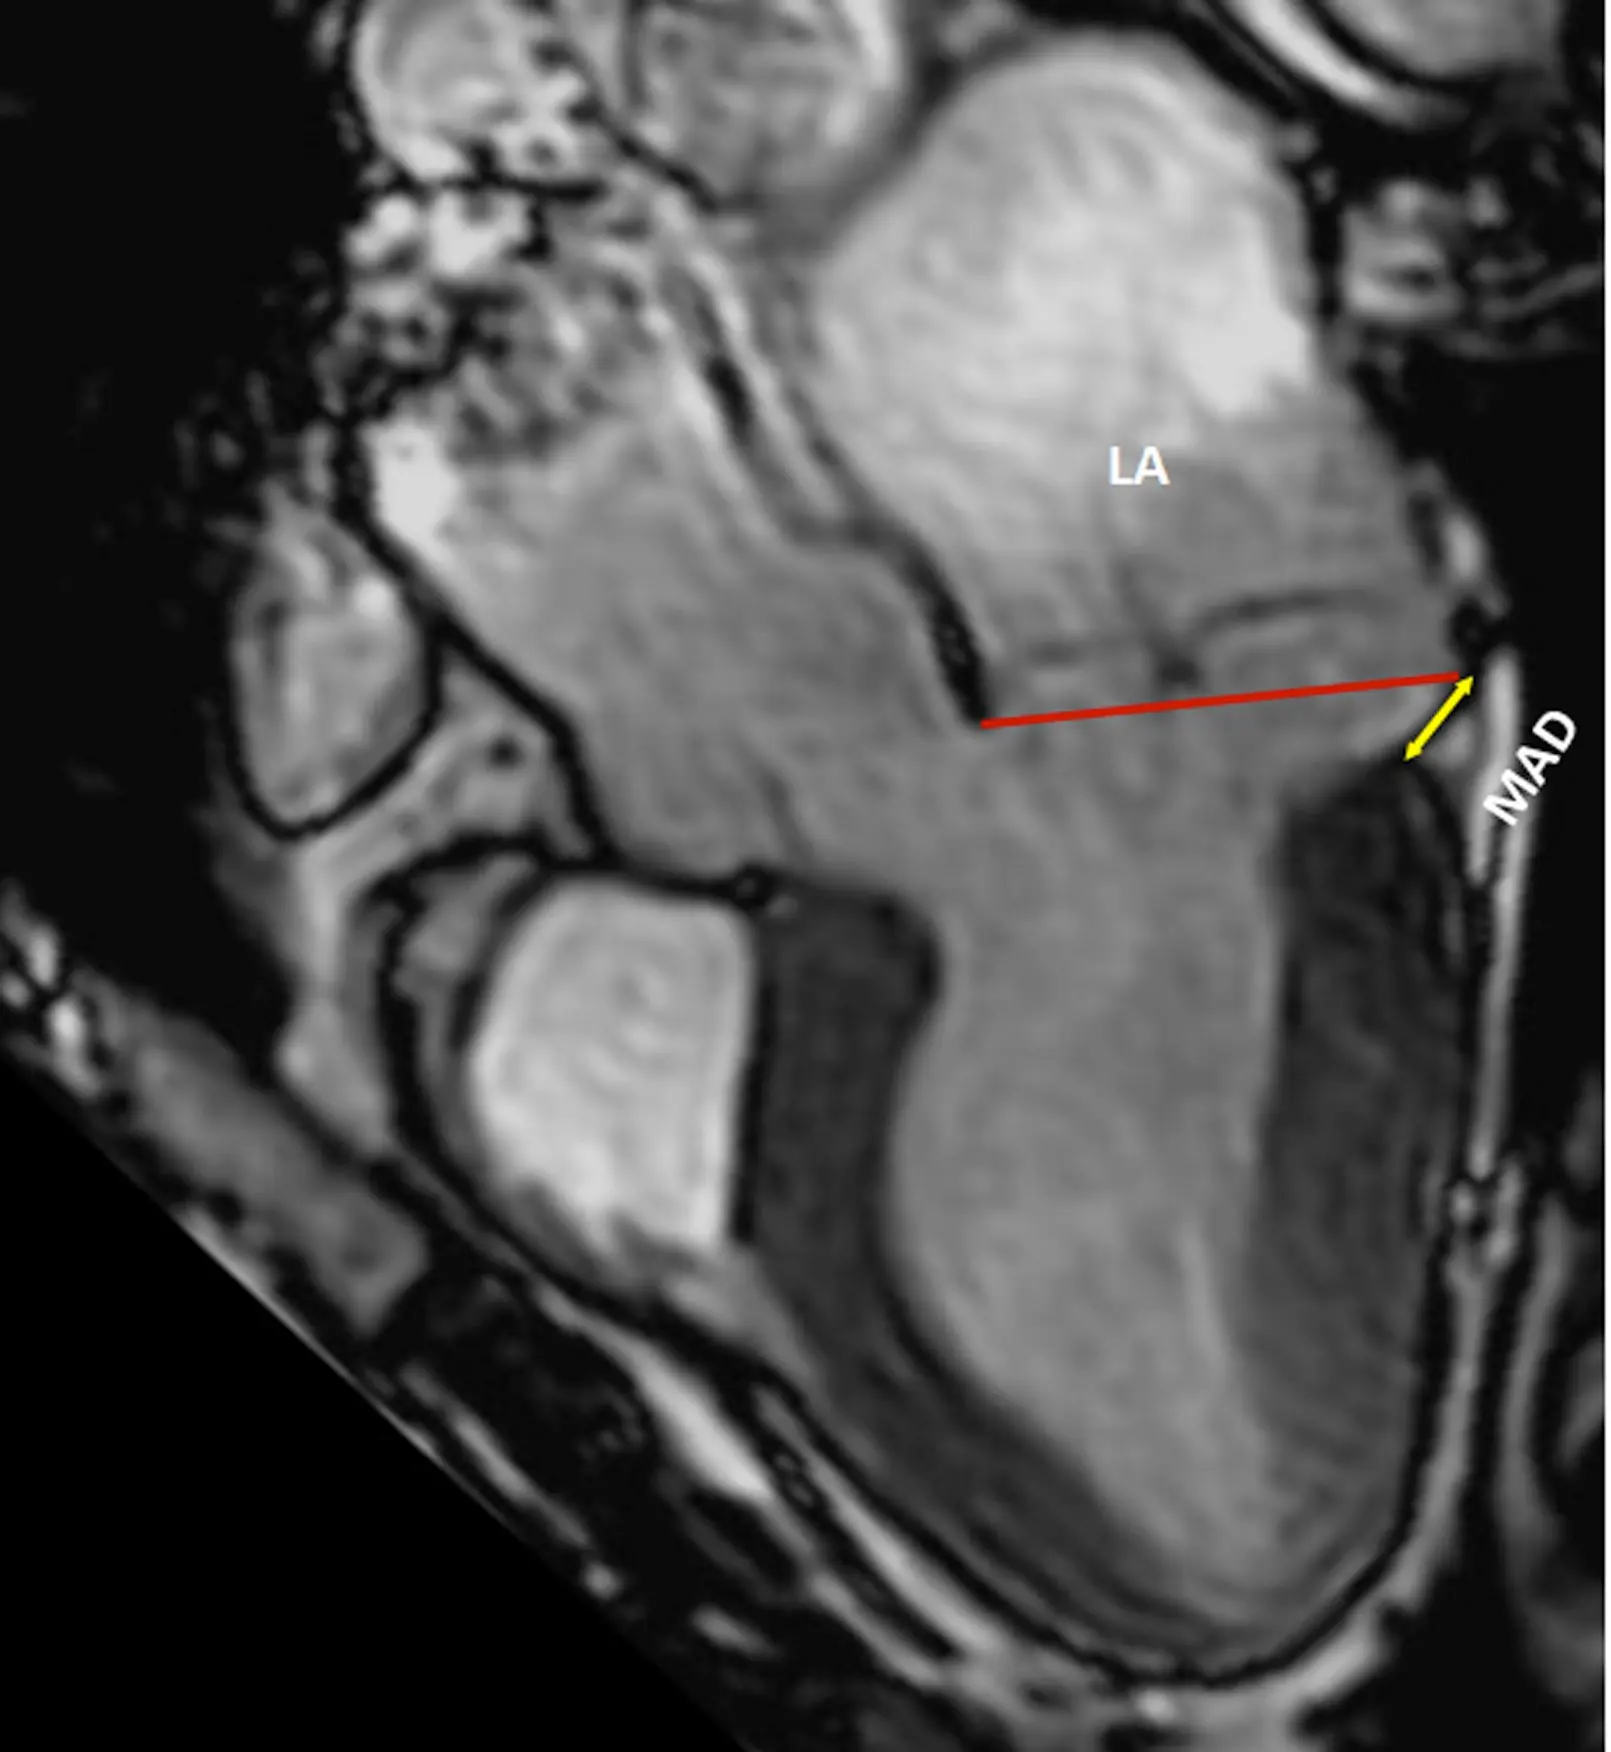

• MAD length is measured in the parasternal long axis view (or equivalent sagittal views on CMR), from the insertion of the posterior leaflet on the detached mitral annulus to the border of the bulging LV myocardium.

Figure source: 1. TTE long-axis view in end-systole displaying bileaflet mitral valve prolapse with (A) MAD (yellow line) of 11 mm length vs. (B) without MAD. The red line indicates the plane of the mitral annulus.

• The upper limit of MAD is defined at the level of posterior leaflet insertion on the annulus/left-atrial-wall, whereas the lower limit is defined at the level of the LV myocardium

• The ventricular myocardium, having lost its basal attachment, bulges more apically than normal, forming the apical margin of the MAD trench